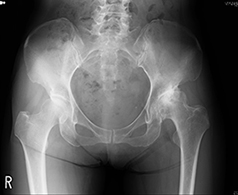

股関節は、大腿骨の骨頭と臼蓋という骨盤のくぼみからなる球関節(ボールと受け皿の関節)です。骨頭が臼蓋にはまり込む構造のため、足を様々な方向へ動かすことができます。関節の表面は軟骨に覆われ、関節のスムーズな動きを可能にしています。

加齢性の変化や外傷などにより軟骨が減少すると、すり減った軟骨の下のむき出しになった骨同士がこすれ合い、炎症が生じ痛みを感じます。

軟骨の減少により股関節の痛みが生じる疾患を変形性股関節症と呼びます。本邦における変形性股関節症の患者は約500万人とも言われ、多くの方がお悩みの疾患です。歩行中や階段昇降時の痛みや、関節の動かせる範囲が減少し靴下をはきにくい・正座ができないなどの症状を生じます。

加齢によって減少した軟骨は元に戻すことは出来ませんが、筋力トレーニングやストレッチなどのリハビリ、薬物療法、体重の減量などの保存療法が一般的に効果的です。保存療法で効果がなく、日常生活動作が著しく制限されている場合に、手術が必要になります。以下に代表的な手術療法である人工股関節全置換術(THA)を説明します。